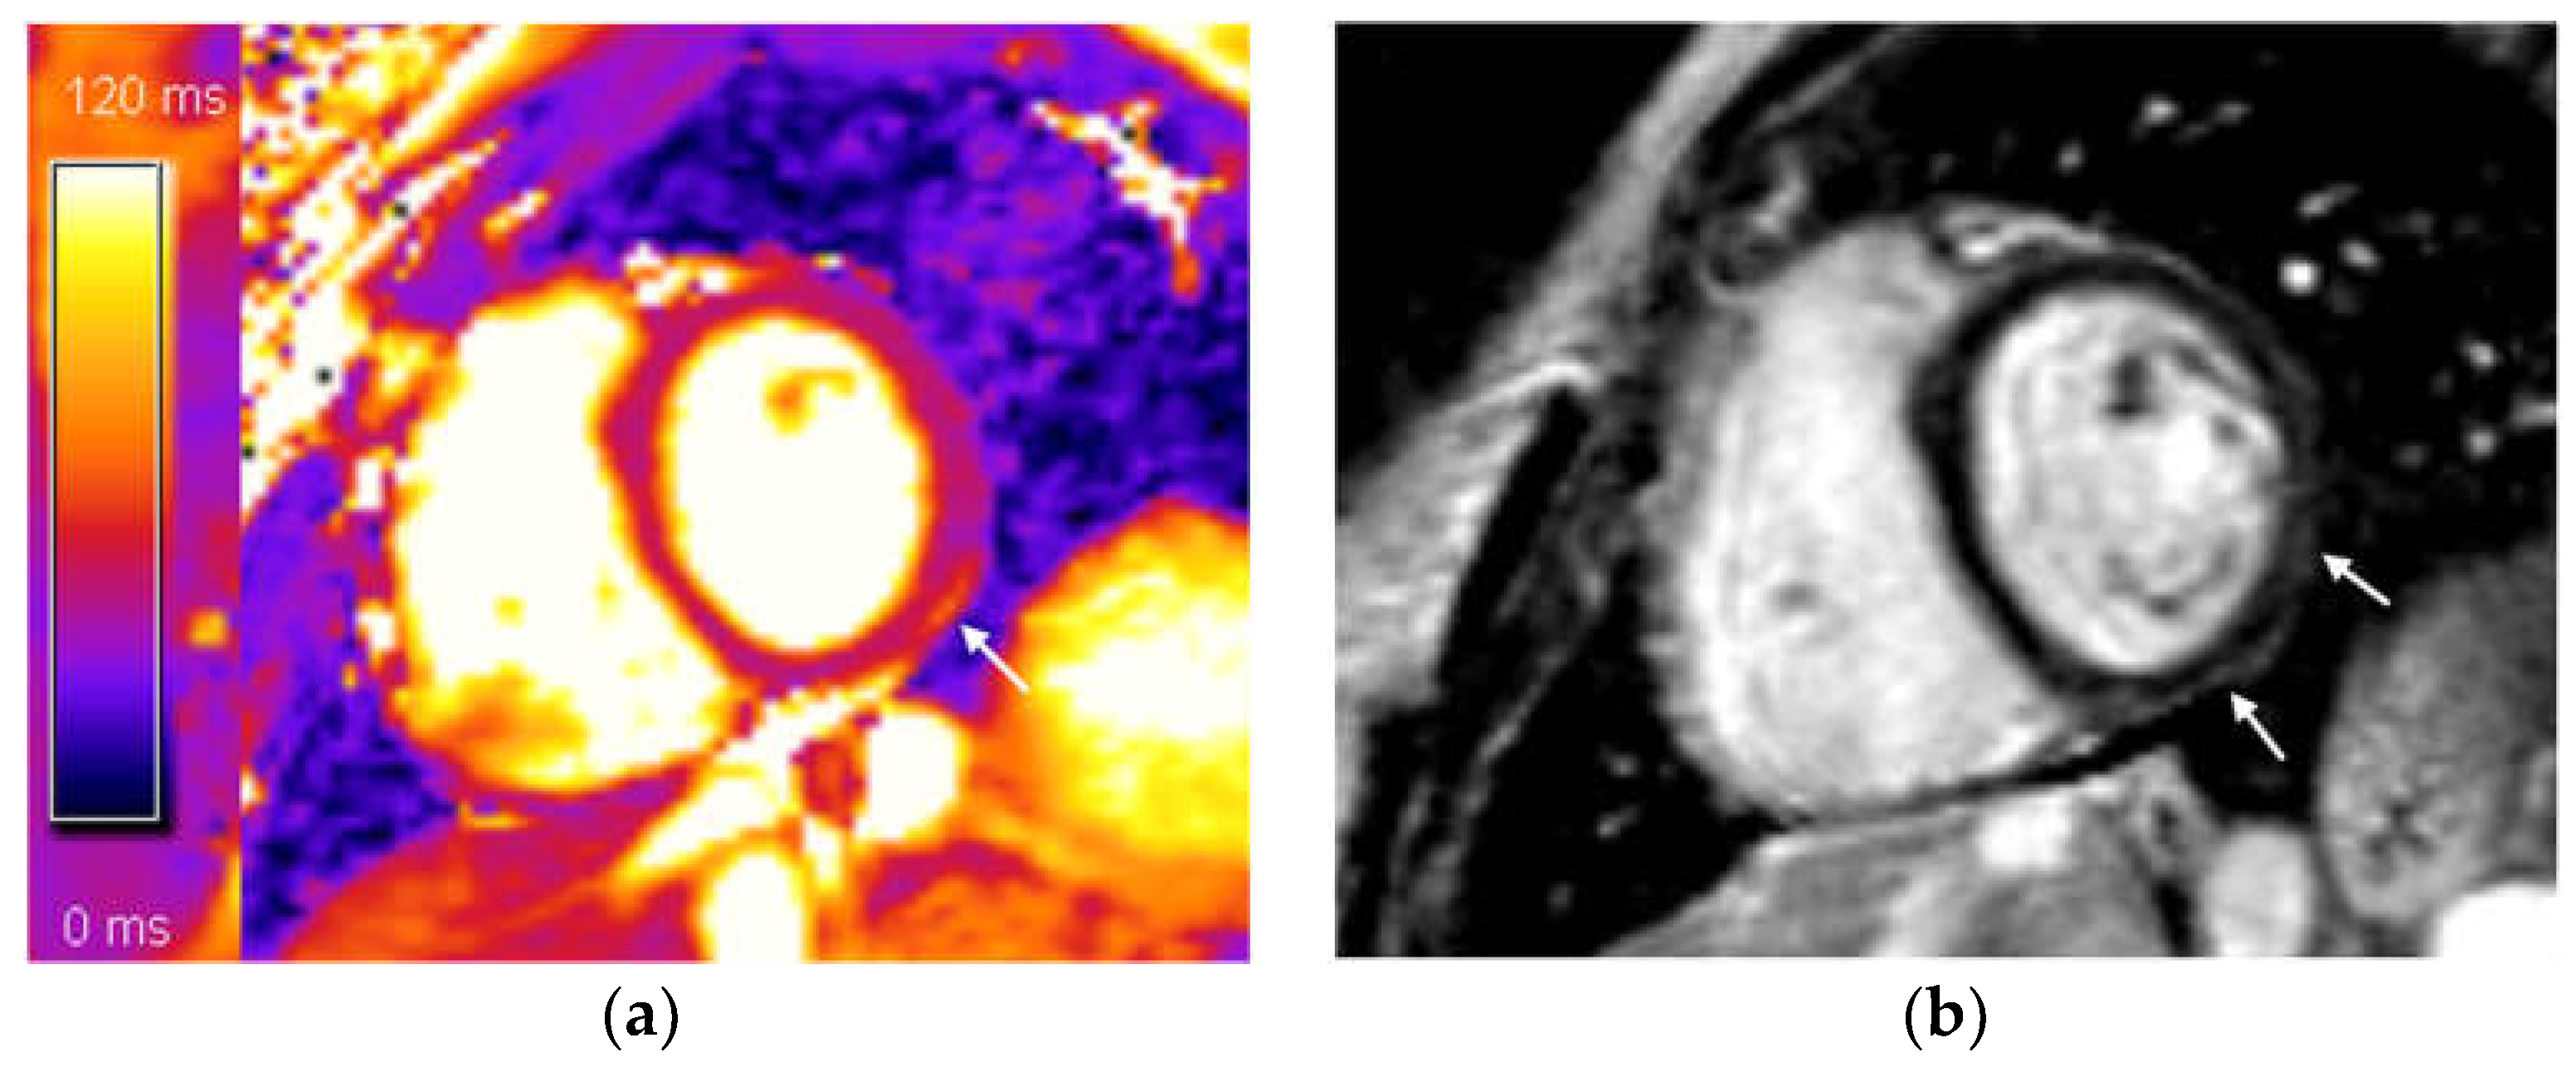

Our research findings suggest that acute myocarditis is relatively uncommon, as it was diagnosed in only a small number of patients. A minority (n = 12; 14.1%) had signs of myocardial edema, indicative of acute myocardial injury. In nearly all of these patients (n = 11; 12.9%), LGE was observed with a subepicardial and/or mid-wall distribution, meeting the 2018 Lake Louise criteria for diagnosing myocarditis (Figure 2) [16]. However, one patient with myocardial edema did not fully meet the criteria for myocarditis, presenting only with a T2-based marker for myocardial edema, from the modified Lake Louise criteria. This edema might be attributed to increased vascular permeability, potentially due to endothelial angiotensin-converting enzyme 2 (ACE2), which serves as a receptor for SARS-CoV-2 entry into host cells [28,29,30,31]. Additionally, some patients with myocarditis (n = 7; 8.23%) also presented with pericardial effusion. Both patients with confirmed myocarditis and those with myocardial edema generally had normal or mildly reduced left ventricular (LV) ejection fraction, an important prognostic marker in myocarditis [32].

Figure 2.

(a) T2 mapping, mid-ventricular short axis slice: increased focal T2 value, subepicardial distribution—a sign of subepicardial myocardial edema in the mid inferolateral segment (marked with arrow); (b) phase-sensitive inversion recovery (PSIR), mid-ventricular short axis slice: subepicardial (non-ischemic) distribution of late gadolinium enhancement (LGE) in mid inferior and mid inferolateral segments (marked with arrows). These CMR findings fulfilled both Lake Louise 2018 criteria for CMR diagnosis of acute myocarditis.